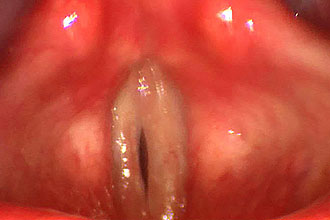

Для диагностики применяется ларингоскопия, во время которой наблюдаются гиперемия, отек слизистой оболочки, а также белесоватые, серые или зеленые пленки.

Попытки самостоятельно удалить пленки с поверхности слизистой могут привести к образованию открытых ран и кровоточивости.